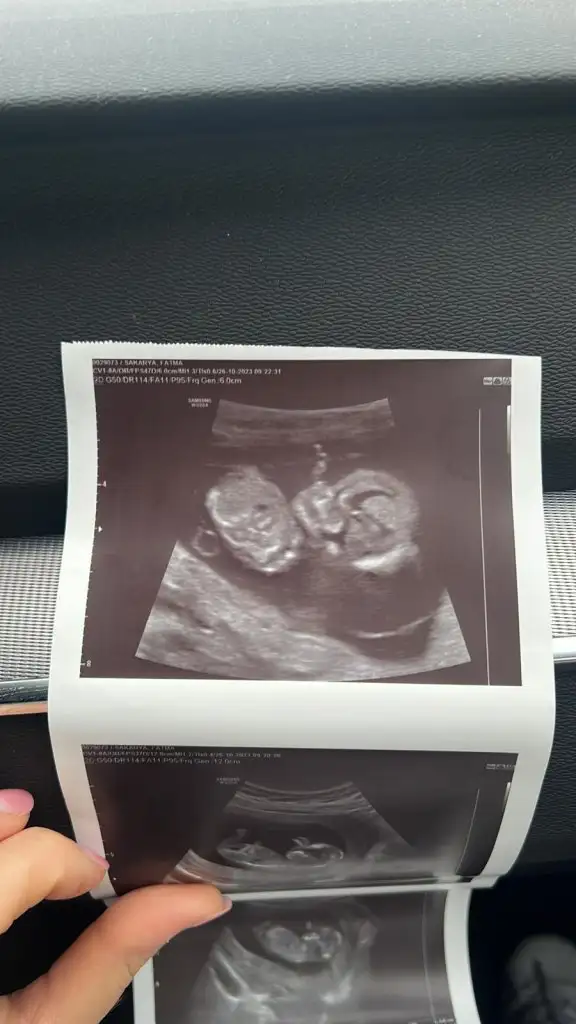

12 haftalik bakarmisiniz cinsiyete?

Eklentiler

• IMG-20231026-WA0002.webp

31,3 KB · Görüntüleme: 44

• IMG-20231026-WA0001.webp

18,8 KB · Görüntüleme: 49

• IMG-20231026-WA0000.webp

15,9 KB · Görüntüleme: 46